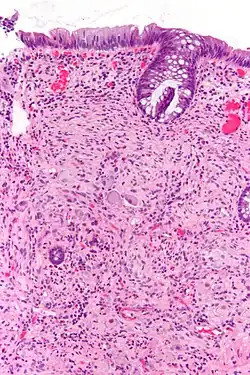

Micrograph of a ganglioneuroma with the characteristic ganglion cells. H&E stain.

Pathologically, ganglioneuromas are composed of ganglion cells, Schwann cells and fibrous tissue.[6] Ganglioneuromas are solid, firm tumours that typically are white when seen with the naked eye.